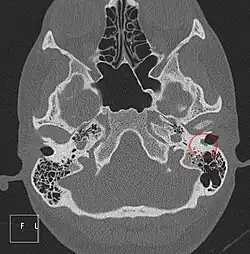

Weiterhin werden Computertomographie-Aufnahmen (CT) angefertigt. Hierzu hat sich die hochauflösende Spiral-Computertomographie als Verfahren der ersten Wahl etabliert. Damit gelingt es, die zarten morphologischen Strukturen der Felsenbeinregion zur Darstellung zu bringen, einer Region, die allerhöchste Anforderungen an die räumliche Auflösung und die Bildqualität von CT-Abbildungen verlangt. Durch die hochauflösende Computertomographie (HR-CT; engl. high resolution computed tomography) kommen die anatomischen Strukturen in der Dünnschichttechnik und der Darstellung im Knochenfenster, in axialer und koronarer Ebene zur Darstellung. Die Grundlage einer hochauflösenden Felsenbein-CT ist die axiale Projektionsebene.[22]

Aufhellungen, also ein dunkler Bereich auf einem Röntgenbild, der sich auf das Mittelohr oder auch dem Antrum mastoideum projiziert, sind häufig mit dem Cholesteatom assoziiert. Im fortgeschrittenen Verlauf eines Cholesteatoms kann radiologisch etwa ein großer rundlicher Defekt (als dunkler Bereich im Röntgenbild nach Schüller) im Bereich des Antrum mastoideum gesehen werden, ferner finden sich häufig Anzeichen einer stärkeren Sklerose des Knochens im Warzenfortsatz. Dies ist der radiologische Ausdruck einer durch die entzündlichen Vorgänge im Cholesteatom ausgelösten chronischen Mastoiditis.[30]